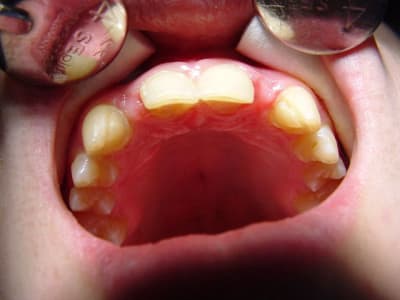

préparations pour bridge collé ...des commentaires?

tu fais un léger retour vestibulaire en mésial des canines, tu ne crains pas que ça devienne visible?

sinon occlusion? et ça parait bien.

pas vraiment de retour mais je souhaitais modifier légèrement l'aspect morpho des canines,

l'occlusion était un peu serrée au niveau des centrales ,mais il y a agénésie des 41 et 31 et j'ai remodelé le bridge collée antagoniste provisoire.

La 13 semble avoir une limite trop vestibulaire en effet...faudra voir le collage final...